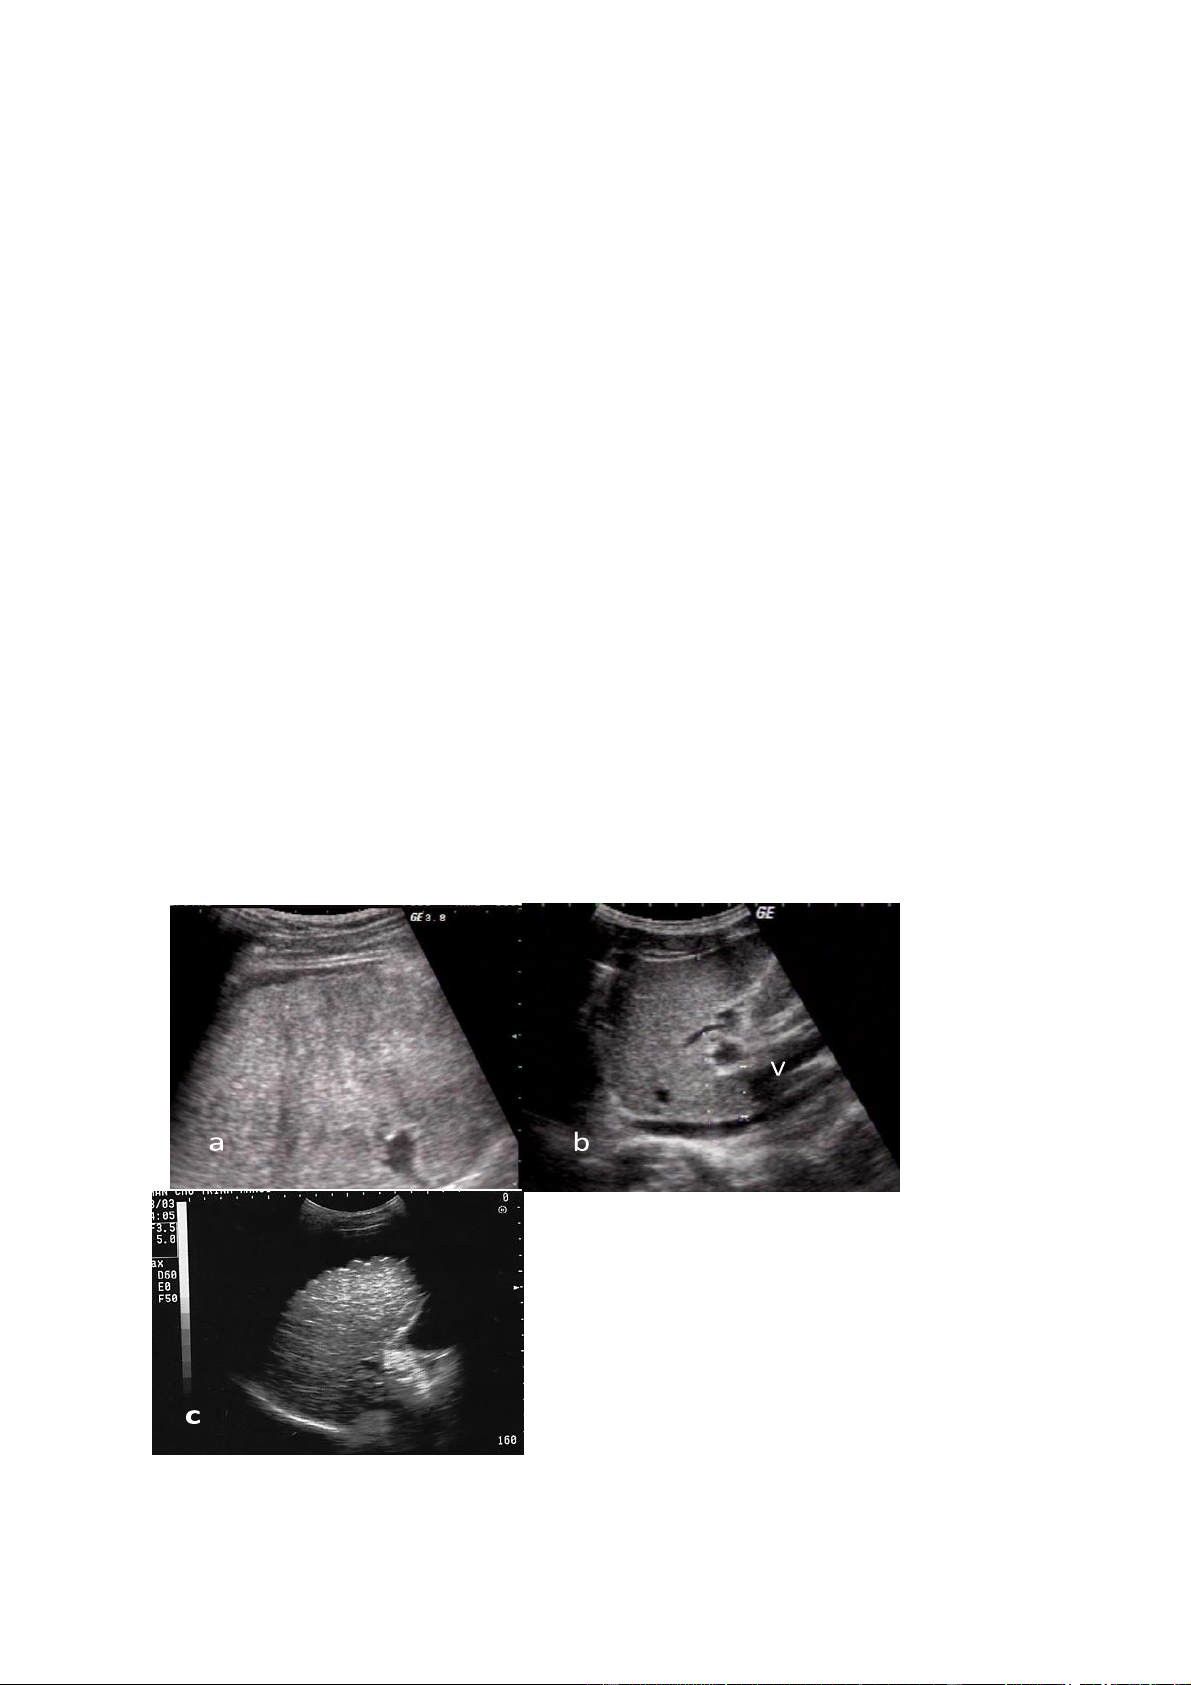

3. CÁC KHỐI U GAN LÀNH TÍNH 3.1.Nang gan

Chẩn đoán xác định

Nang gan biểu hiện bằng vùng rỗng âm tròn hoặc bầu dục với hình tăng âm

phía sau. Thành nang mảnh và rõ nét. Nhu mô gan xung quanh nang hoàn toàn bình thường.

Thường có một hoặc hai nang. Trong trường hợp nhiều nang thì hình ảnh

siêu âm của mỗi nang không thay đổi. Một số các trường hợp gan đa nang thường

kèm theo thận đa nang gọi là bệnh gan-thận đa nang, đôi khi kèm theo tụy đa nang.

Bệnh gan-thận đa nang thường có tính chất gia đình.

Hình.3.1. a. Nang gan điền hình không có vách với hình rỗng âm và tăng âm phía

sau; b. Nang gan có vách ngăn. 3.2.U máu gan